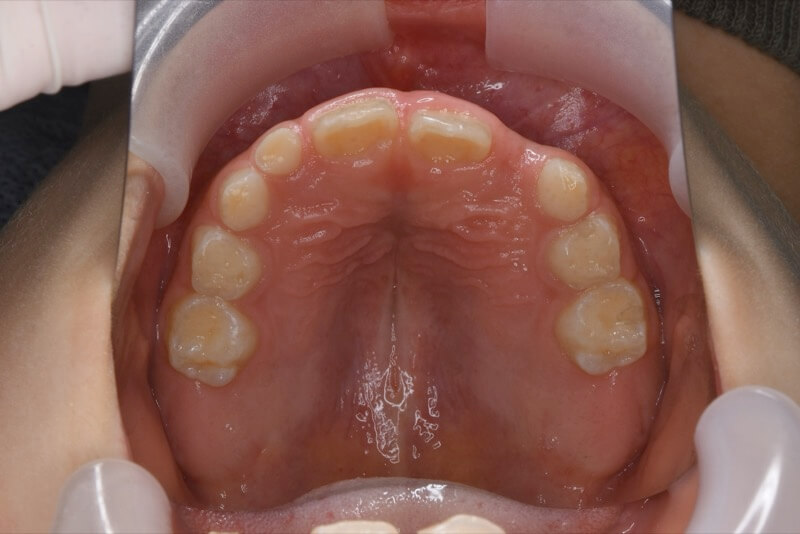

治療前

前歯が反対に咬んでいる。

前歯部反対咬合

前歯の反対咬合を可撤式の装置で改善しました。引き続き永久歯列完成まで経過を追って治療致します。